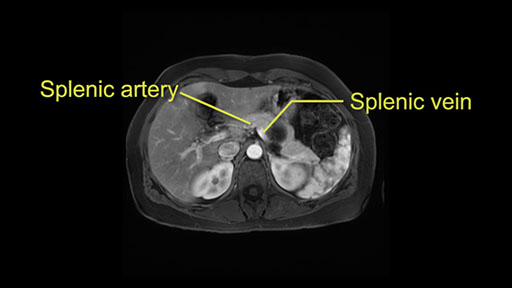

The second slowing down moment or consideration I give to a distal pancreatectomy is the anatomy of the portal vein and the splenic artery. And so I look here and the anatomy is pretty straightforward. The splenic vein comes off normally and runs behind the pancreas and I can see the artery superior to that, again coming off in a normal manner from the celiac axis. So those two things, the portal vein and the splenic artery will be taken normally in this procedure.

The third consideration in a distal pancreatectomy is whether I take the spleen or preserve it and I will try to always preserve it if I can. If it can be done safely and without too much difficulty or risk of bleeding. So the couple of considerations on the imaging that I look at is: Is the tail of the pancreas firmly embedded in the hilum of the spleen? I can see here that it isn’t and that it would likely be possible to preserve the spleen and I also look at the vessels and see whether the vessels are kind of firmly kind of intertwined in the distal part of the tail or whether we think we can actually separately take them with a stapler and remove all the tip of the tail of the spleen. So I think this would be a good candidate for a Warshaw technique, which is not preserving the splenic vein or artery but rather taking them as a segment and preserving the spleen. After this, the spleen would be getting all the blood supply from the short gastrics of the stomach. So that’s the third consideration in a distal pancreatectomy and the final thing is the retroperitoneum.